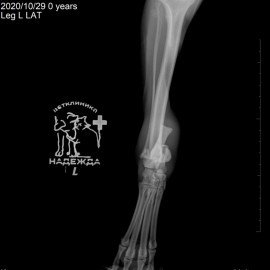

Рентгенологический снимок после проведенной операции.